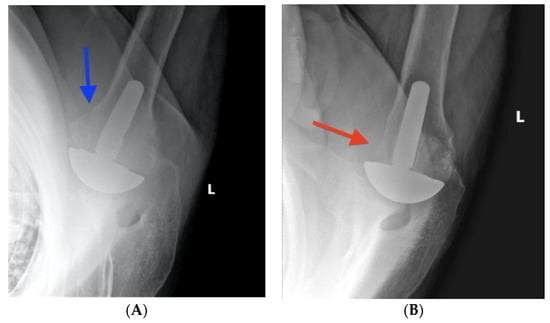

2.2. Surgical Technique

2.3. Radiographic Evaluation